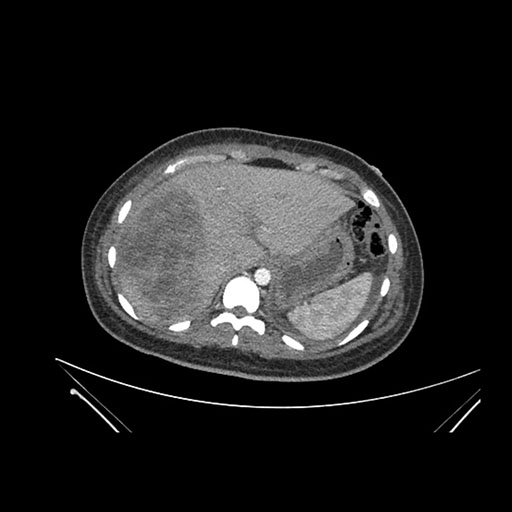

Imaging Analysis

Look through the patient's CT scan to identify any areas of concern for the necessary procedure.

Based on initial findings, which issue(s) would you be most concerned about?